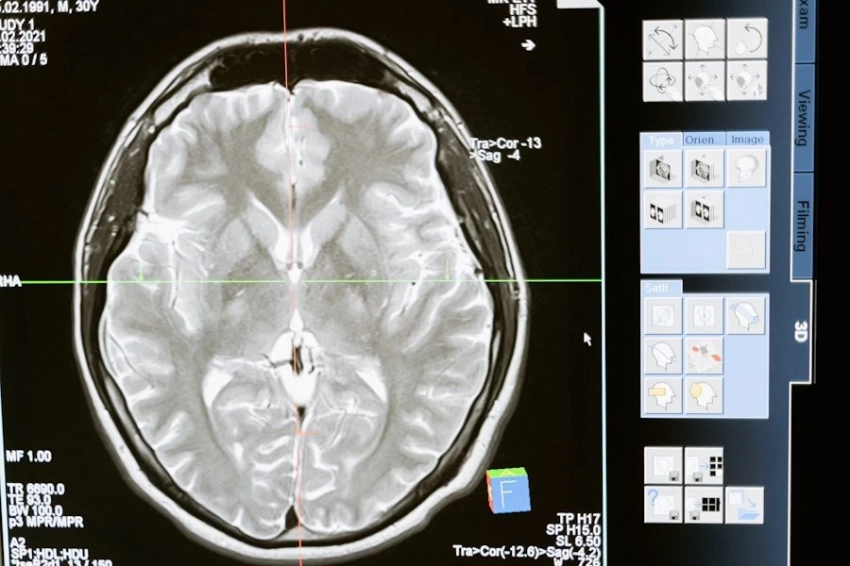

В рамках проводимых экспериментов на лабораторных грызунах, ученые имплантировали им клетки рака легкого человека и проводили тестирование в трех различных вариантах введения астанина-211: в кровь, прямо в опухоль, или с зондом. Так, при использовании зонда с радионуклидом, опухоли распространялись примерно в три раза меньше, а при введении астанина-211 в кровь выживаемость подопытных составила 80%. Наилучший же результат показал метод введения вещества непосредственно в опухоль, при котором выживаемость составила все 100%.